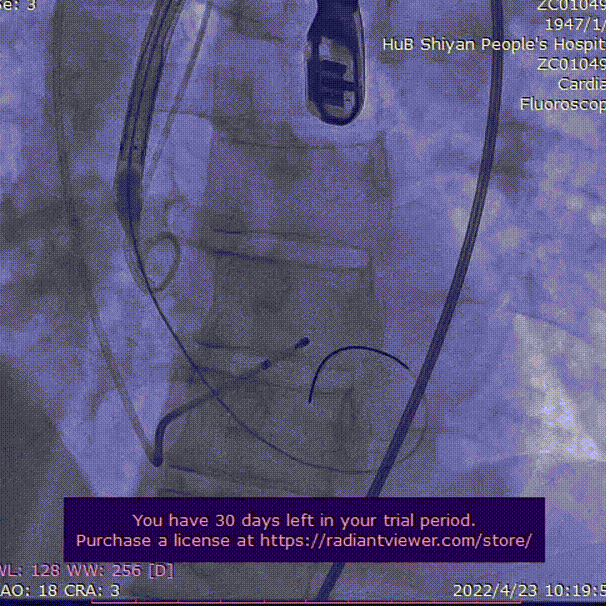

根部造影

输送器过弓

造影定位

瓣膜工作位评估

瓣膜完全释放

术后根部造影评估

•根据当前影像资料及测量数据,推荐跨瓣角度为LAO 18° CRA 3° (右窦中心)左右。

•推荐预装AV26瓣膜,释放角度推荐RAO 3° CAU 29° (左右重合)左右,推荐瓣环下2mm左右释放。

•瓣膜释放至工作位(2/3)后建议调整至左冠切线位( LAO 28° CRA 28°左右 )进一步确定人工瓣膜稳定性。瓣膜释放过程操作难度适中,要求团队密切配合,充分利用瓣膜系统部分及完全回收功能。